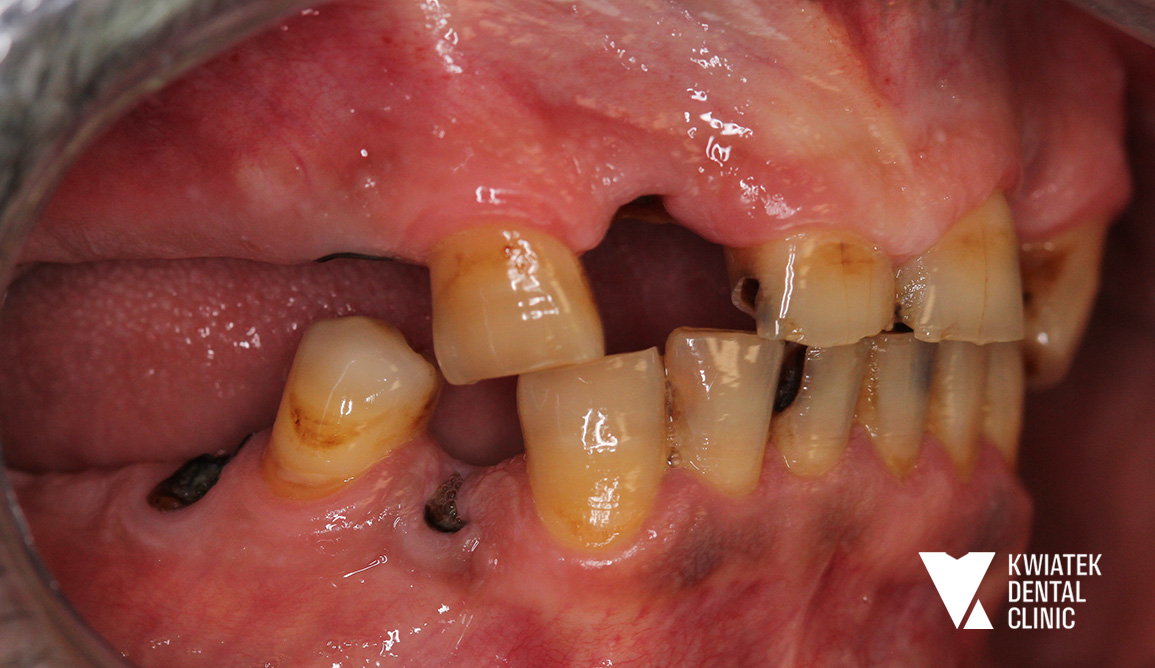

PRZED

Pacjent zgłosił się do naszej Kliniki z potrzebą całościowego przywrócenia funkcji i estetyki uzębienia. Leczenie rozpoczęliśmy od profesjonalnej higienizacji, aby usunąć złogi nazębne oraz płytkę bakteryjną, co stworzyło prawidłowe warunki do dalszych zabiegów.

Następnie wykonano leczenie endodontyczne (kanałowe) zębów kwalifikujących się do odbudowy protetycznej, eliminując przy tym stany zapalne.